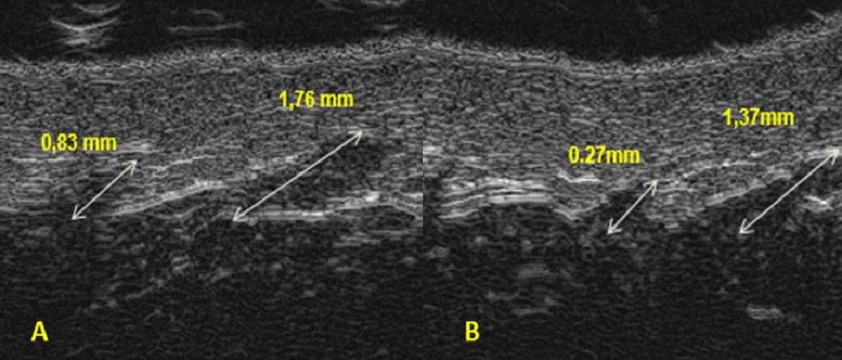

USG a redukcja cellulitu

W przypadku terapii mających na celu redukcję cellulitu najbardziej użytecznym parametrem jest pomiar długości lub pola powierzchni pasm tkanki podskórnej wrastających w skórę właściwą tzw. zębów cellulitowych. Alternatywą do ich pomiaru może być pomiar długości granicy między tkanką podskórną a skórą właściwą. Opcje te zazwyczaj są dostępne w ultrasonografach stosowanych w badaniach skóry. Jeżeli korzystamy tylko z aparatu klasycznego, wówczas dokonanie oceny ilościowej jest utrudnione, gdyż zęby cellulitowe są mniej widoczne. Nie wyklucza to jednak oceny ilościowej, która polega na ocenie wizualnej przebiegu granicy między skórą właściwą a tkanką podskórną. Wielkość zębów cellulitowych koreluje ze stopniem zaawansowania zmian w postaci guzków i nierówności skóry oraz klinicznymi skalami oceny cellulitu. Jak wskazują wyniki licznych badań, jeżeli prowadzona terapia jest skuteczna, dochodzi do zmniejszenia pola powierzchni/długości zębów cellulitowych oraz długości granicy między skórą właściwą a tkanką podskórną (rys. 1). Niniejsza granica staje się bardziej równa. Zmiany obserwowane w ultrasonografie korelują ze zmniejszeniem stopnia nasilenia cellulitu i prowadzą do poprawy wyglądu skóry pacjenta. Bardzo istotnym parametrem w ocenie skuteczności terapii dotyczących ciała jest również pomiar grubości tkanki podskórnej. W przypadku wielu z prowadzonych terapii zależy nam na tym, by tkanka podskórna uległa zmniejszeniu (rys. 2). Ultrasonografia jest tu jedyną metodą, która umożliwia bezinwazyjnie dokonanie rzetelnego pomiaru tej struktury. Należy jednak pamiętać, że dokonanie pomiaru tkanki podskórnej możliwe jest tylko za pomocą ultrasonografów klasycznych, co wynika z zasady, że im wyższa częstotliwość głowicy, tym niższa penetracja ultradźwięków w głąb tkanek. Ponadto ultrasonografia pozwala nam obserwować zmiany zachodzące w strukturze tkanki podskórnej w wyniku prowadzonych terapii.